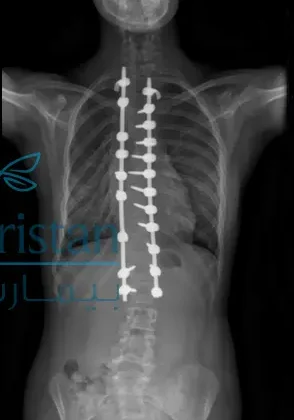

زاوية كوب هي المقياس الطبي الأساسي الذي يستخدمه الأطباء لتحديد درجة انحناء العمود الفقري في حالات اعوجاج العمود الفقري.

يتم قياسها باستخدام الأشعة السينية، حيث تُرسم خطوط على الفقرات الأكثر ميلًا في أعلى وأسفل الانحناء، ثم تُحسب الزاوية بين هذه الخطوط.

عند أي زاوية كوب تصبح الجراحة ضرورية؟

بشكل عام، تُناقش الجراحة عادة عندما تتجاوز زاوية كوب 45 إلى 50 درجة، خاصة في الحالات التالية: